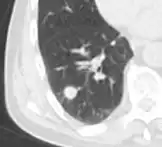

- In case of calcifications, a popcorn-like appearance indicates a hamartoma, which is benign.[3]

- In case of subsolid nodules, being part solid has a higher risk of cancer than being purely ground glass opacity.

-

Part solid nodule.[9] -

Ground glass opacity nodule.[9]